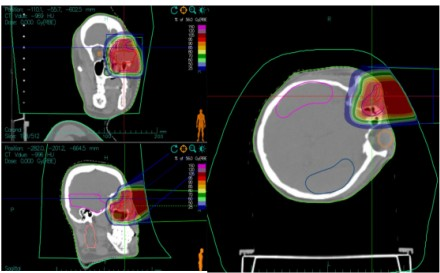

With years of clinical experience and superb heavy ion therapy technology, Director Li Xiaojun developed an individualized heavy ion therapy treatment plan for the patient. On July 20, 2022, the patient underwent carbon ion radiotherapy (uniform scanning). Because the tumor was adjacent to important organs such as the eyeball and optic nerve, a two-stage treatment plan was designed to further increase the radiation dose to the tumor area and reduce the dose to critical organs.

The first-stage plan treated the tumor and subclinical areas. The patient was positioned in the lateral decubitus position, and two horizontal fields were irradiated at couch angles of 0° and 325°.

The second-stage plan targeted the residual tumor area. The patient was positioned in the supine position, and a vertical field was used for irradiation to protect the eyeball.

Figure 1: Case 1 – Dose Distribution Map of Carbon Ion Therapy for a Patient with Lacrimal Sac Squamous Cell Carcinoma (First Course)

Figure 1: Case 1 – Dose Distribution Map of Carbon Ion Therapy for a Patient with Lacrimal Sac Squamous Cell Carcinoma (Second Course)